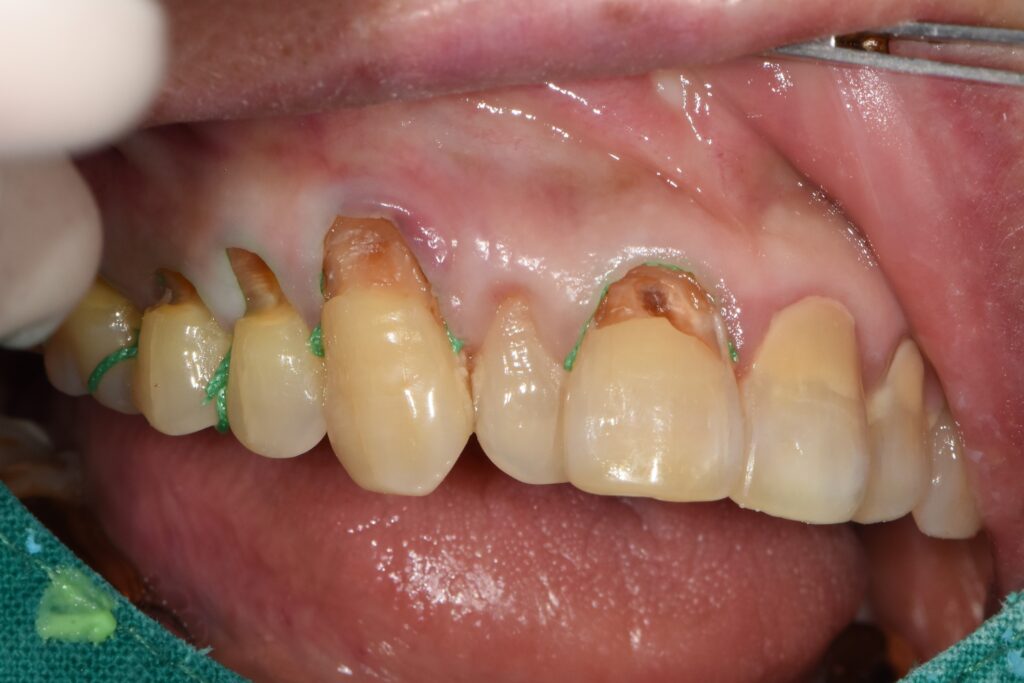

1) #46 임플란트 1차 수술 + GBR(간단)

수술 당일에는 동의서 작성 후, 국소마취(침윤) 하에

오스템 SSIII 계열 임플란트(직경 5.0, 길이 10mm)를 식립했습니다.

- 골질: D2

- 초기고정: 약 40N

- 동종골 기반 GBR(간단) 동반

- 보철 계획: 약 3개월 후 보철 진행

즉, “뼈가 아주 넉넉해서 그냥 심는 케이스”가 아니라,

부족한 부위를 보강해 안정적인 골유착 환경을 만드는 방식으로 접근했습니다.